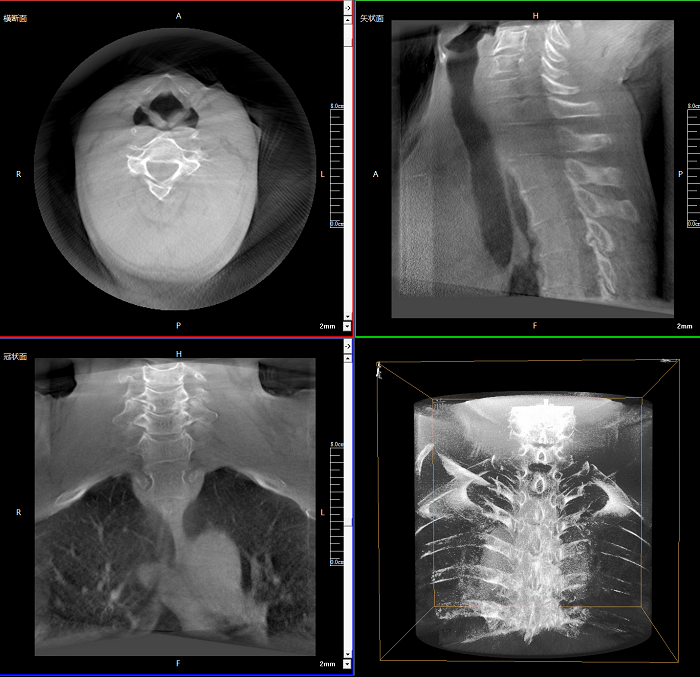

Clinical picture

臨床圖片